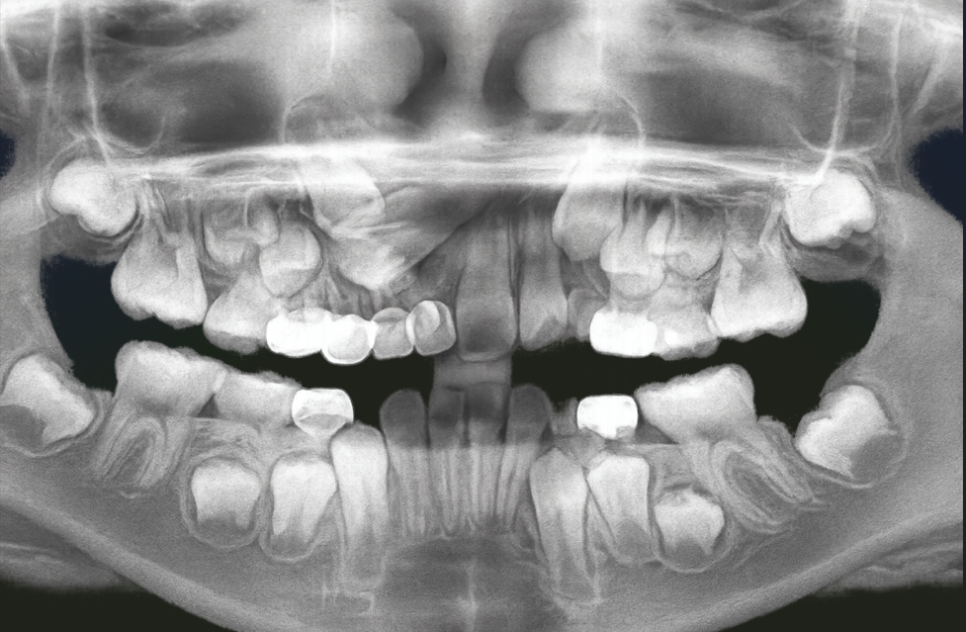

우장산역 치과 구강 정보

우리 아이들도 필요합니다.

만약 유치 충치로 영구치가 올라오기 전에

발치를 해야 된다 판단되면,

예정보다 유치를 이르게 뽑아야 되므로

이에 따른 조치로 이어져야 됩니다.

만약 교환 시기가 얼마 안 남았다면

그냥 지켜봐도 별다른 문제가 없지만,

영구치 씨앗인 치배가 형성되고 있는 단계라면

공간을 유지해 줄 수 있는 장치를 사용해서

추후 치아가 올라올 수 있는 충분한 공간을

확보해 줘야 됩니다.

또한 치아가 매복되어 안 올라오거나,

결손되어 아예 치배가 없는 경우 등

유치에서 영구치로 교환되는 시기

문제가 없는지 꾸준히 체크를 해줘야 됩니다.